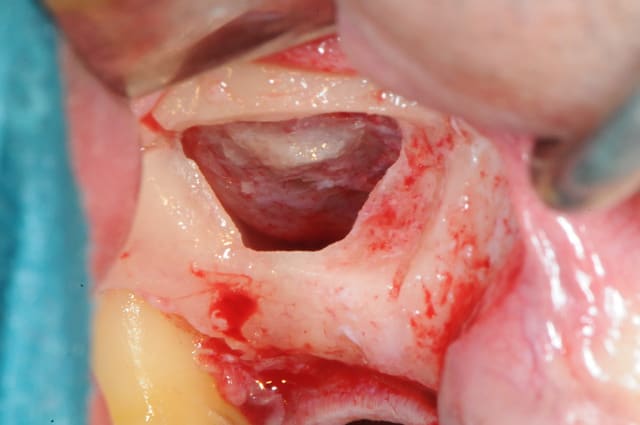

en attendant voici un des deux sinus de ce matin.

MP3 ( chez Pred) en comblement et ROG avec membrane et pins pour palier la forte concavité vestibulaire.